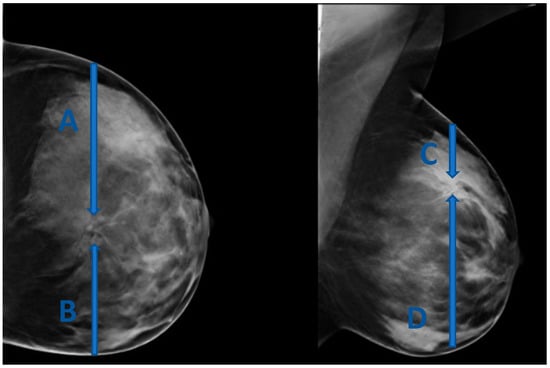

The site of entry in this approach should be determined based on the location of the lesion dictating the shortest skin-to-lesion route. For example, when the lesion is closest to the superior aspect of the breast, a cranio-caudal (CC) approach is favored (Figure 1).

Figure 1. (AD) represent four possible approaches for biopsy of a lesion located in the upper inner aspect of the breast. (C) is the shortest skin-to-lesion route, so a craniocaudal approach should be used.